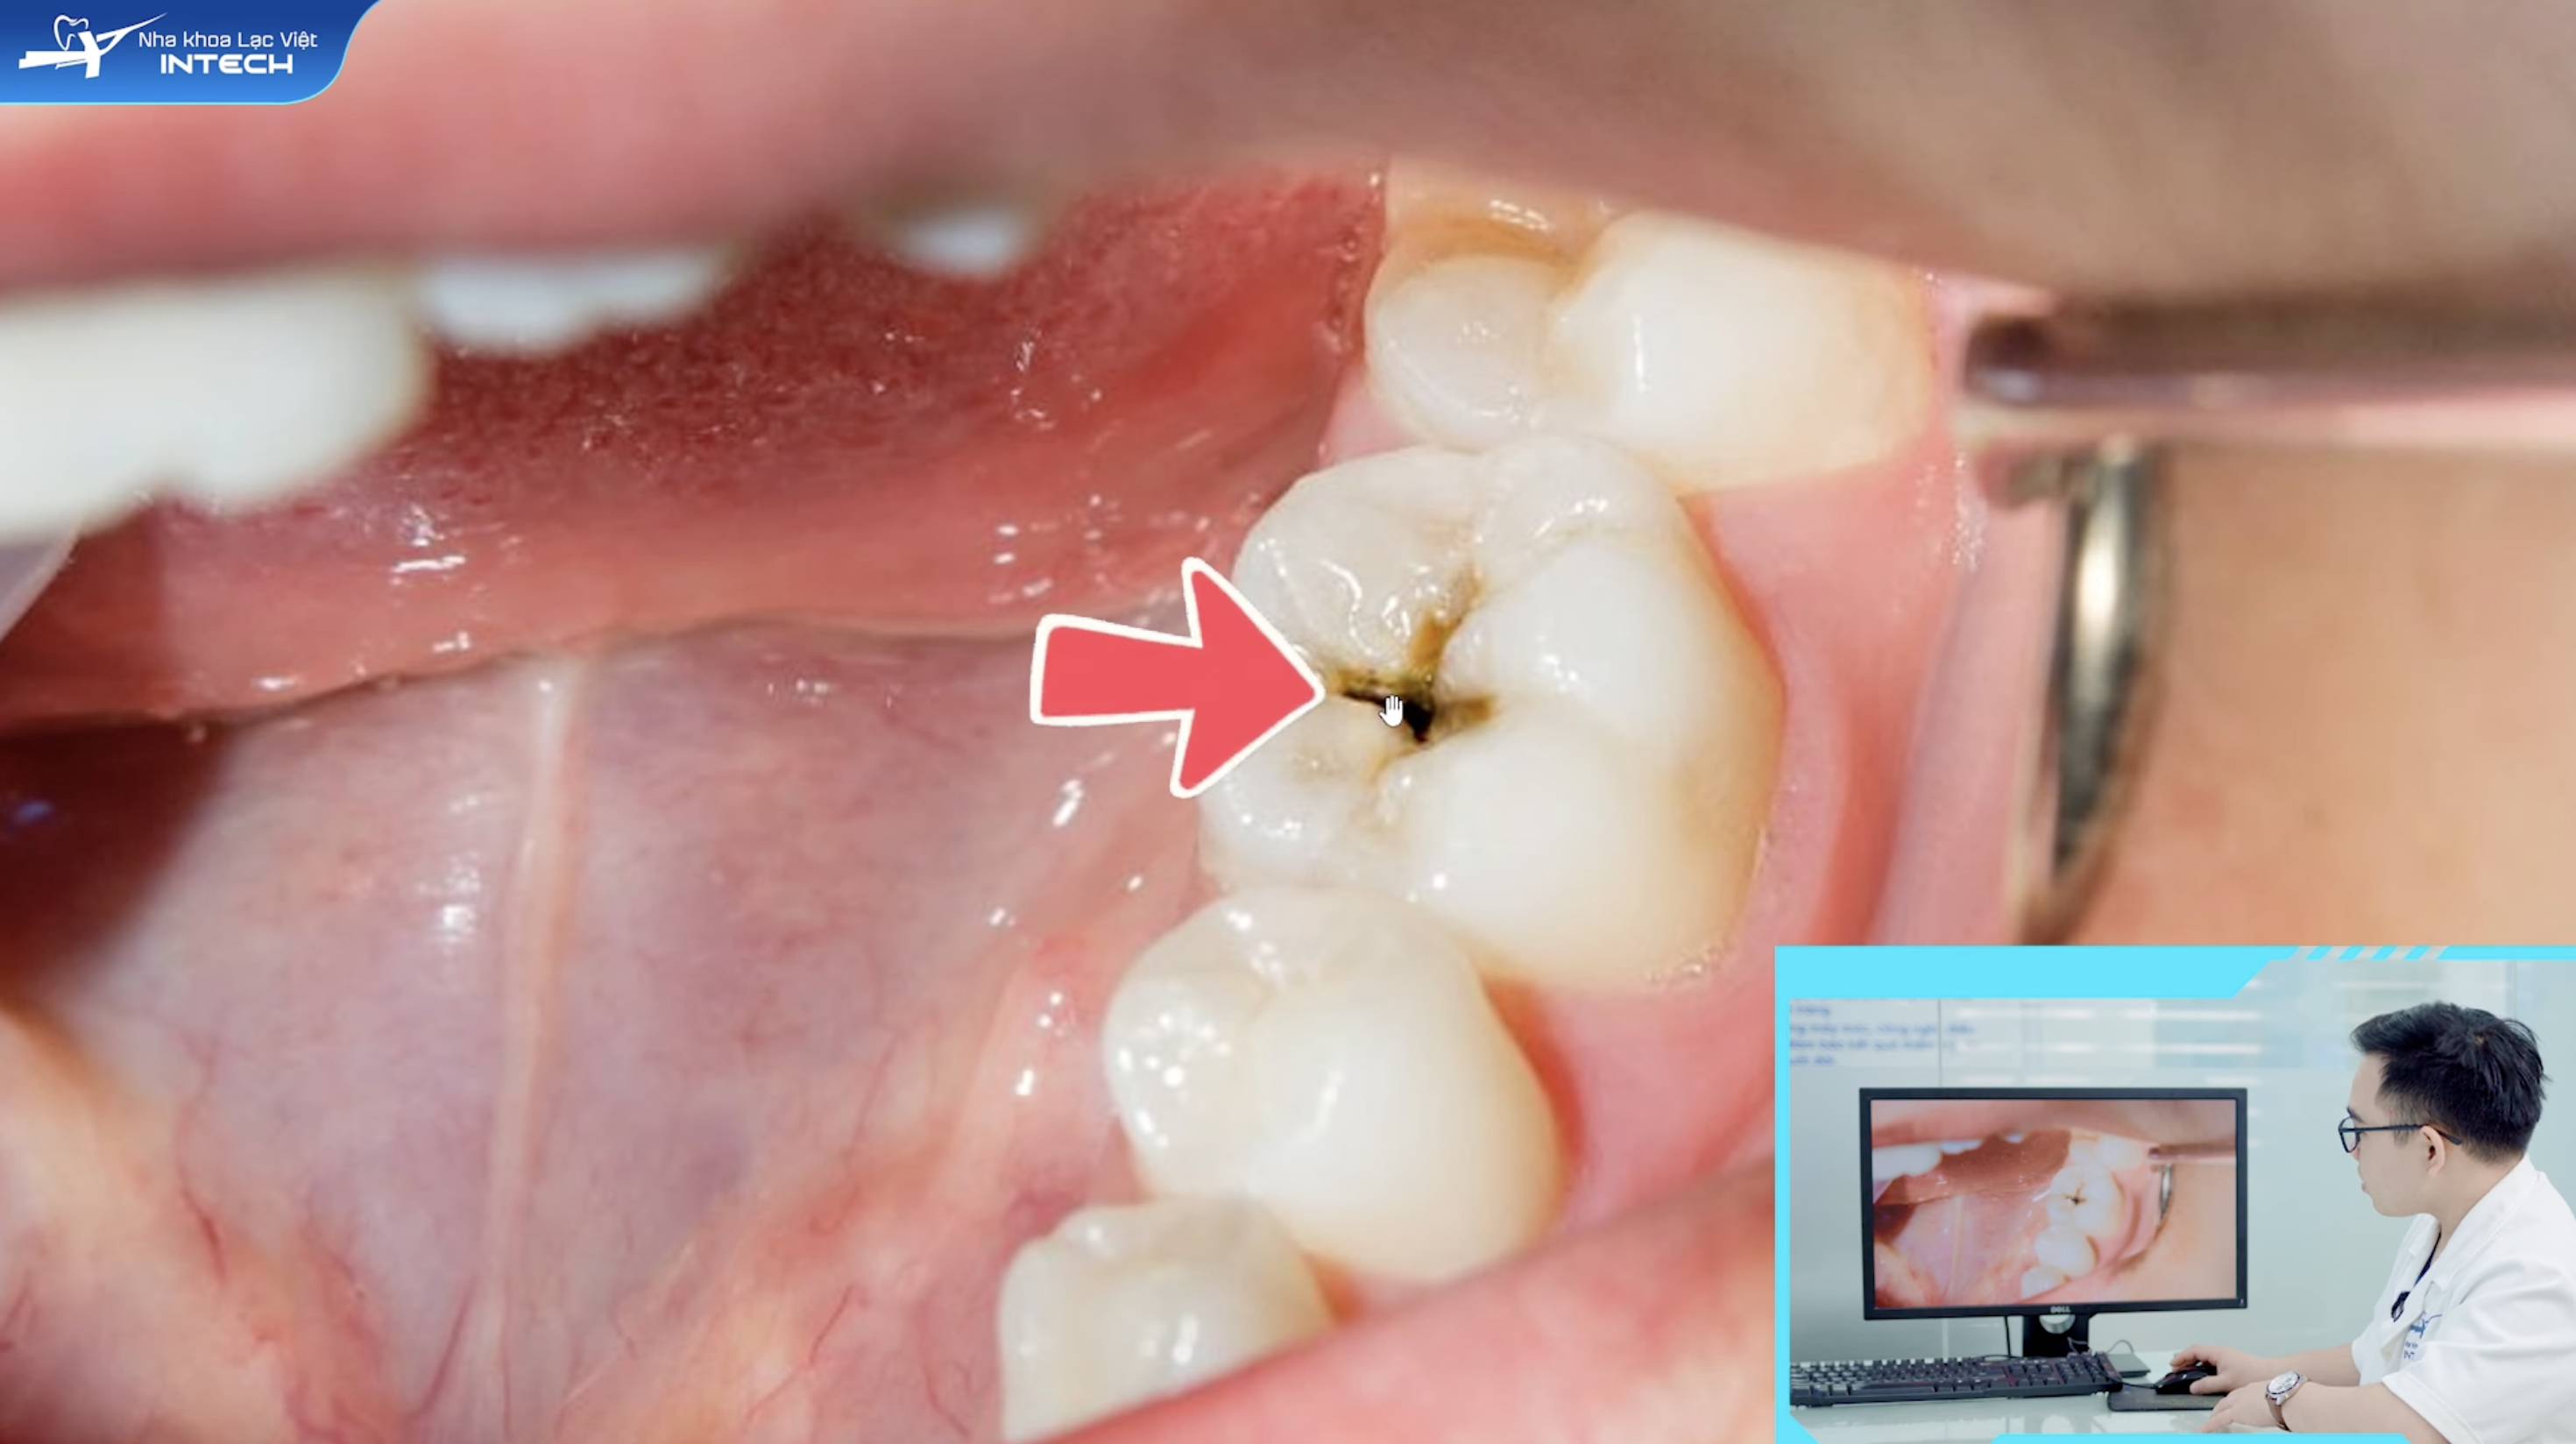

• Nguyên nhân: Lỗ sâu đã ăn sâu vào tủy răng. Vi khuẩn đã tấn công và gây ra nhiễm trùng nặng nề, làm tổn thương vĩnh viễn tủy răng.

• Cách điều trị: Bác sĩ bắt buộc phải tiến hành điều trị tủy răng (nội nha). Quy trình bao gồm việc lấy sạch mô tủy bị viêm, làm sạch và tạo hình ống tủy, sau đó hàn kín bằng vật liệu chuyên dụng. Sau khi điều trị, răng sẽ không còn nguồn nuôi dưỡng nên trở nên giòn và dễ vỡ. Do đó, việc bọc sứ là rất cần thiết để bảo vệ cấu trúc răng và phục hồi chức năng ăn nhai.

• Ví dụ lâm sàng: Bệnh nhân bị sâu một lỗ lớn ở mặt nhai, đã ăn vào tủy. Bệnh nhân có triệu chứng đau nhức dữ dội, kéo dài suốt đêm. Bác sĩ chỉ định điều trị tủy răng và sau đó làm mão sứ để bảo vệ.

Viêm tuỷ không hồi phục khi bệnh nhân có lỗ sâu lớn, đã ăn vào tuỷ